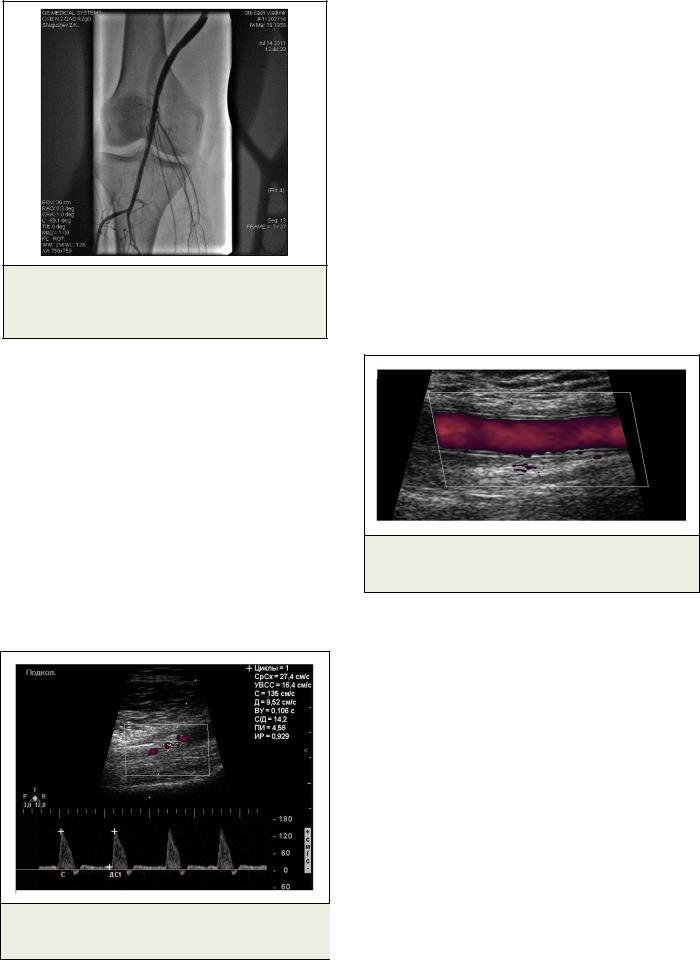

Рис. 6. Ангиография.

Восстановленный просвет подколенной артерии, тибио-перинеального ствола.

(Рис.5). Затем в область дистального анастомоза и в подколенную артерию последовательно были имплантированы стенты Сristalo Ideale 6.0- 9.0-40, Cristalo Ideale 7.0-10.0-40 с полным восстановлением просвета сосудов (Рис. 6).